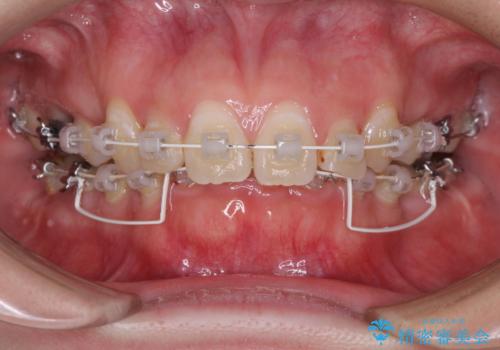

- 審美装置

下顎小臼歯の欠損により過蓋咬合となっていたため、下顎は臼歯を起こすことで咬み合わせを改善し、八重歯は第一小臼歯2本を抜歯し、補助装置を使用して速やかに改善することとしました。

八重歯は3,4か月で速やかに改善されました。